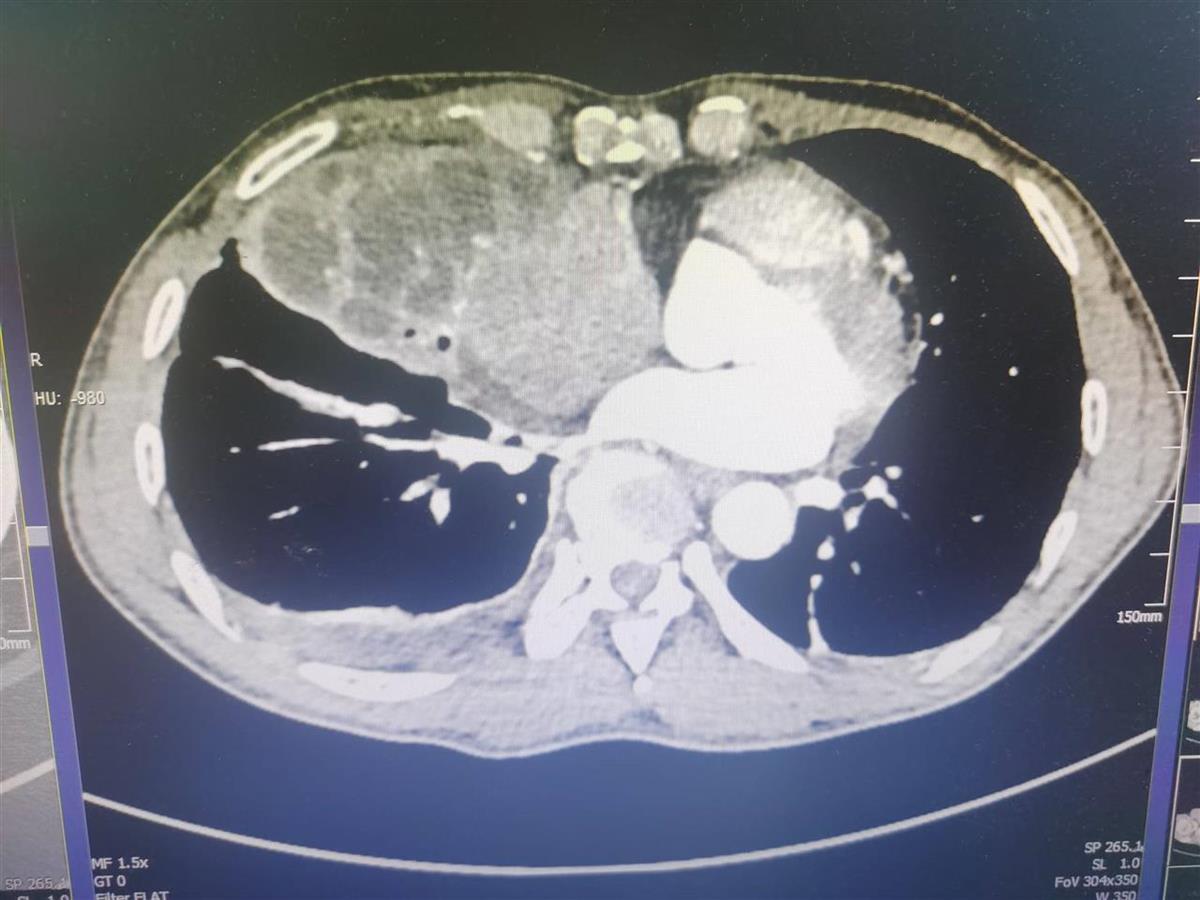

呛入柴油的陈师傅肺内支气管、肺泡等都造成了严重损伤

果然,CT影像下,陈师傅的右肺有大面积低密度区显示,右肺支气管有狭窄,右肺中叶实变明显。该院胸外科参与会诊后认为,可先进行气管镜探查,清理气道分泌物,之后,在控制炎症后,择机进行手术处理。

梅敏慧说,通过CT影像和气管镜探查,可以发现,呛入陈师傅肺内的柴油给支气管、肺泡等都造成了严重损伤。好在通过气管镜清理后,再给予激素类药物抗炎,陈师傅的症状明显改善。返回病房后,陈师傅原先短促的呼吸逐渐变得平稳起来。